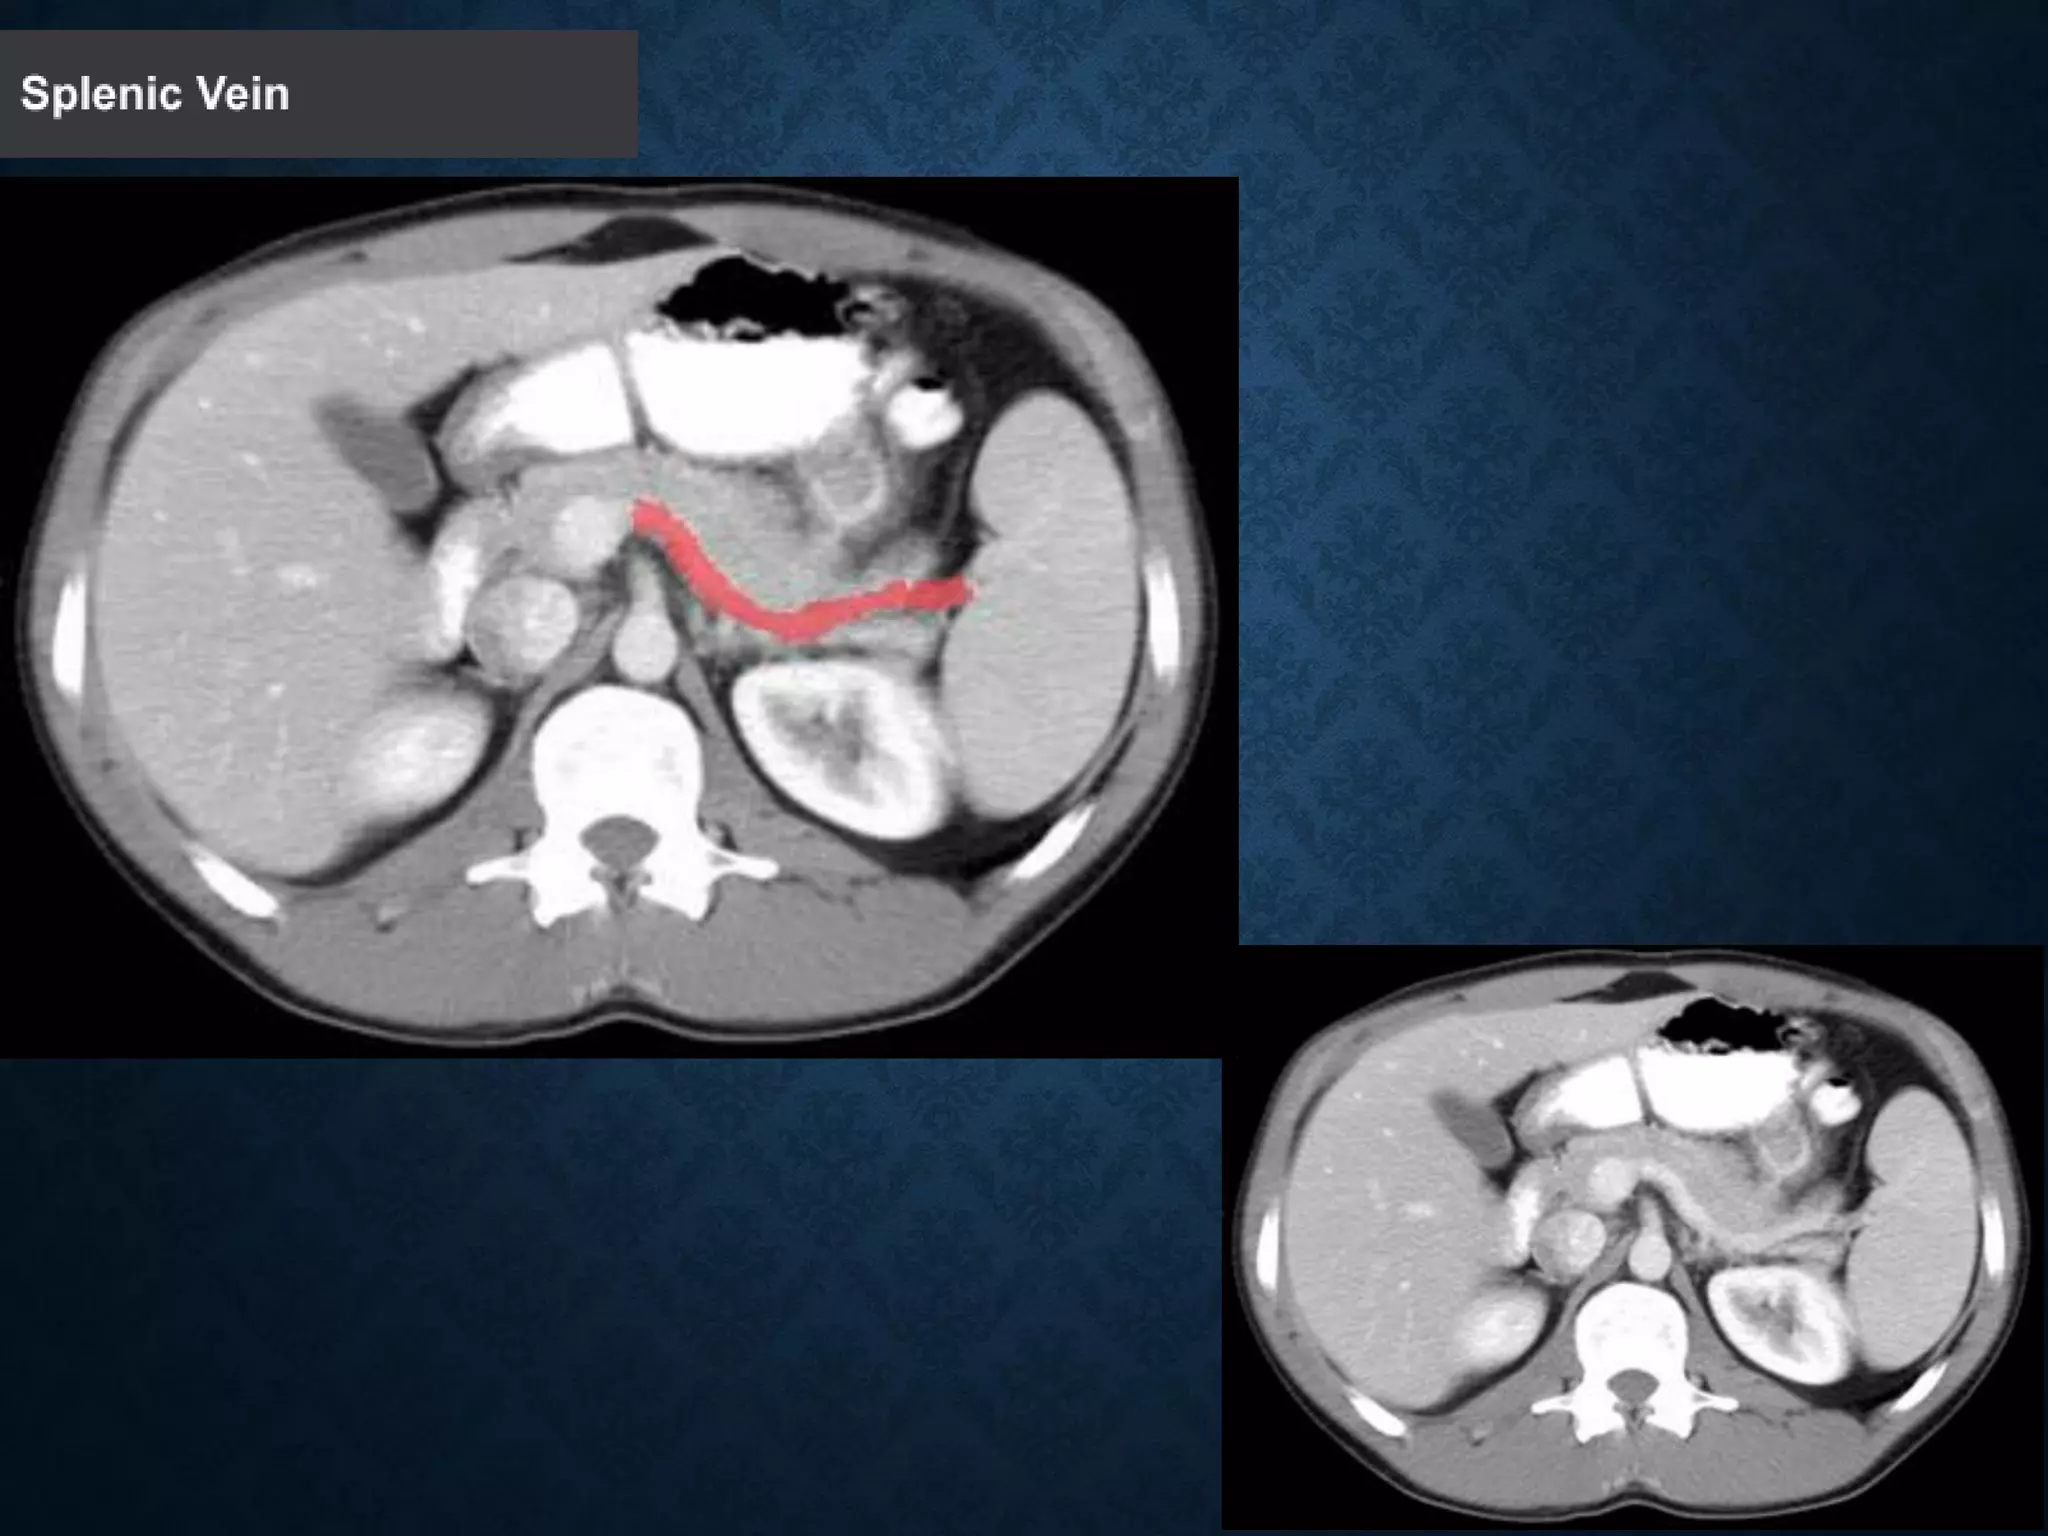

Identify the following structures in the body CT to the right. To view the location of the structure in the image click on

the label at the left and the structure will be indicated in the image. Abdominal CT scans typically begin just above

the diaphragm, so the first slice you see is of the lower chest.